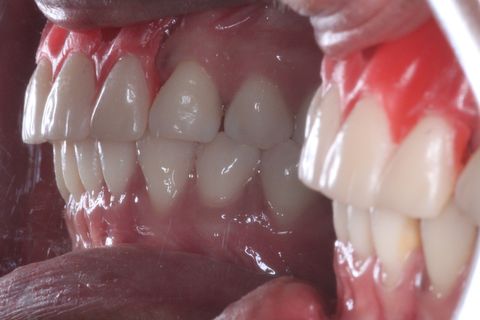

Provisórios instalados . Foto com um ano e meio após a instalação do enxerto e dos implantes. Paciente não compareceu antes para a finalização do trabalho devido problemas particulares

Minipilares instalados. Nota-se apenas 3 minipilares pois um dos implantes foi perdido. Instalamos um novo implante que também foi perdido. Optamos em manter apenas 3 implantes e finalizar a prótese fixa parafusada.

O caso clínico ainda está em andamento. A paciente atualmente está fazendo uso de próteses provisórias e está sendo feito controle gengival para posteriormente serem instaladas a prótese definitivas.